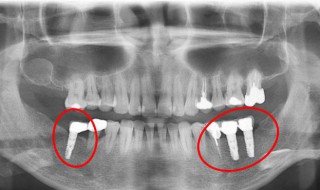

1、给牙齿打桩,是指在牙齿缺损较大,或因为外伤等原因只剩下牙根时,因剩下的牙齿过短或力量过于薄弱,不能用修复体(主要指烤瓷牙)直接修复,需要给牙根里打桩,加固并延长折断的牙齿,以使假牙能获得足够的力量固定。